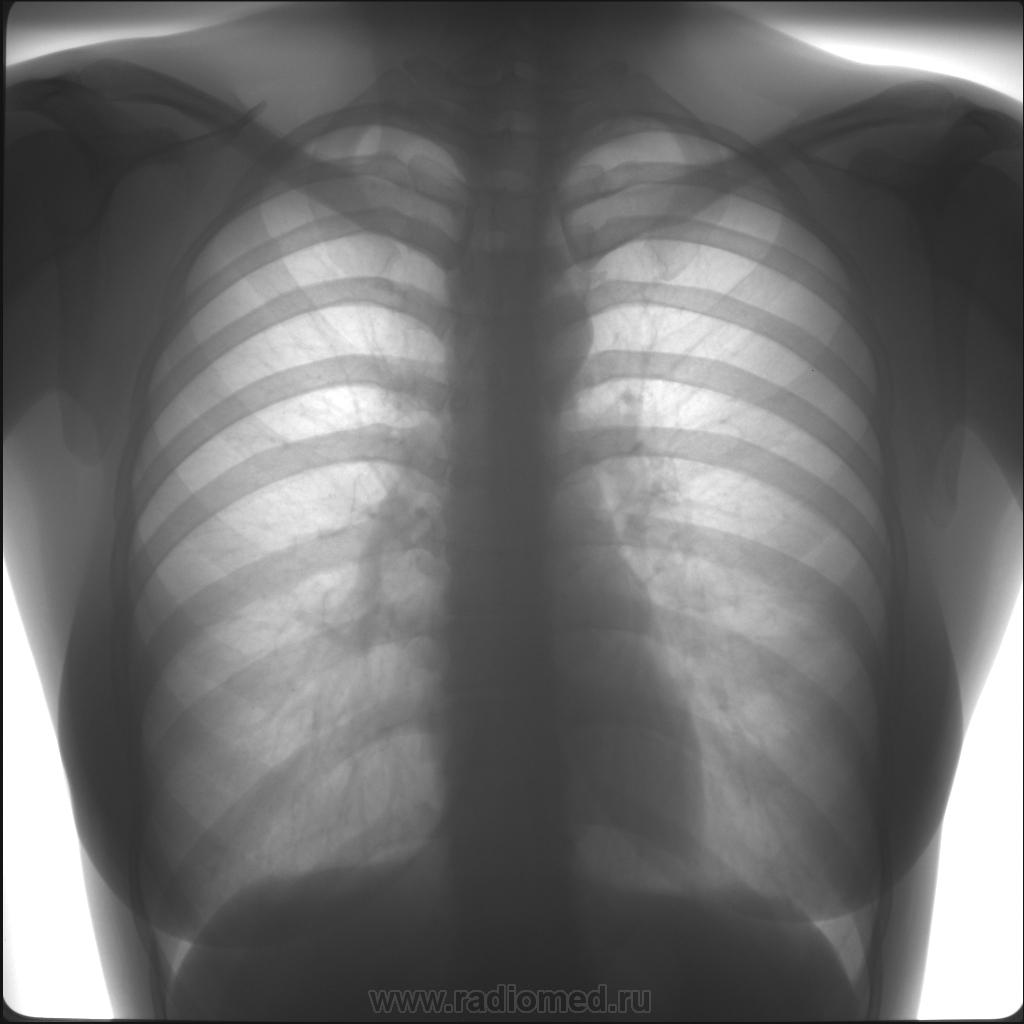

Влияние излучения при флюорографии: что нужно знать?

:max_bytes(150000):strip_icc()/GettyImages-182898594-56816ad75f9b586a9ee8f491.jpg)